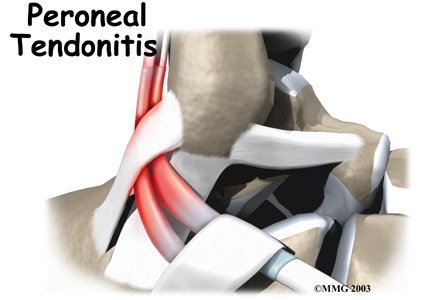

Peroneal Tendon Problems

Problems affecting the two peroneal tendons that lie behind the outer ankle bone (the lateral malleolus) are common in athletes. These problems mainly occur in the area where the two tendons glide within a fibrous tunnel behind the lateral malleolus.